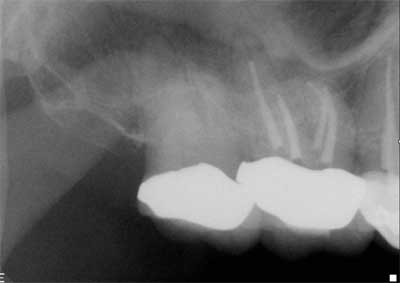

Clinicians rely on a variety of methods to determine working length including, but not limited to, the tactile sensation of feeling the file “pop” through the apex, bleeding on paper points, and radiographs. However, proper use of the EAL, in conjunction with a well-exposed and properly angled preoperative radiograph, will result in the most accurate and reproducible means of determining the true working length. Ideally, this will lead to more predictable and efficient treatment outcomes to maximize both patient comfort and root canal success.On routine six-month recall, the patient was asymptomatic and the access opening was restored. The apical and crestal bone was unremarkable. The follow-up radiograph was taken from different horizontal and vertical angles. Now the fill-in palatal root looks nearly flush with the radiographic apex. A case like this clearly illustrates the limitations of two-dimensional radiographs and the benefits of an EAL for the most accurate working length determination.